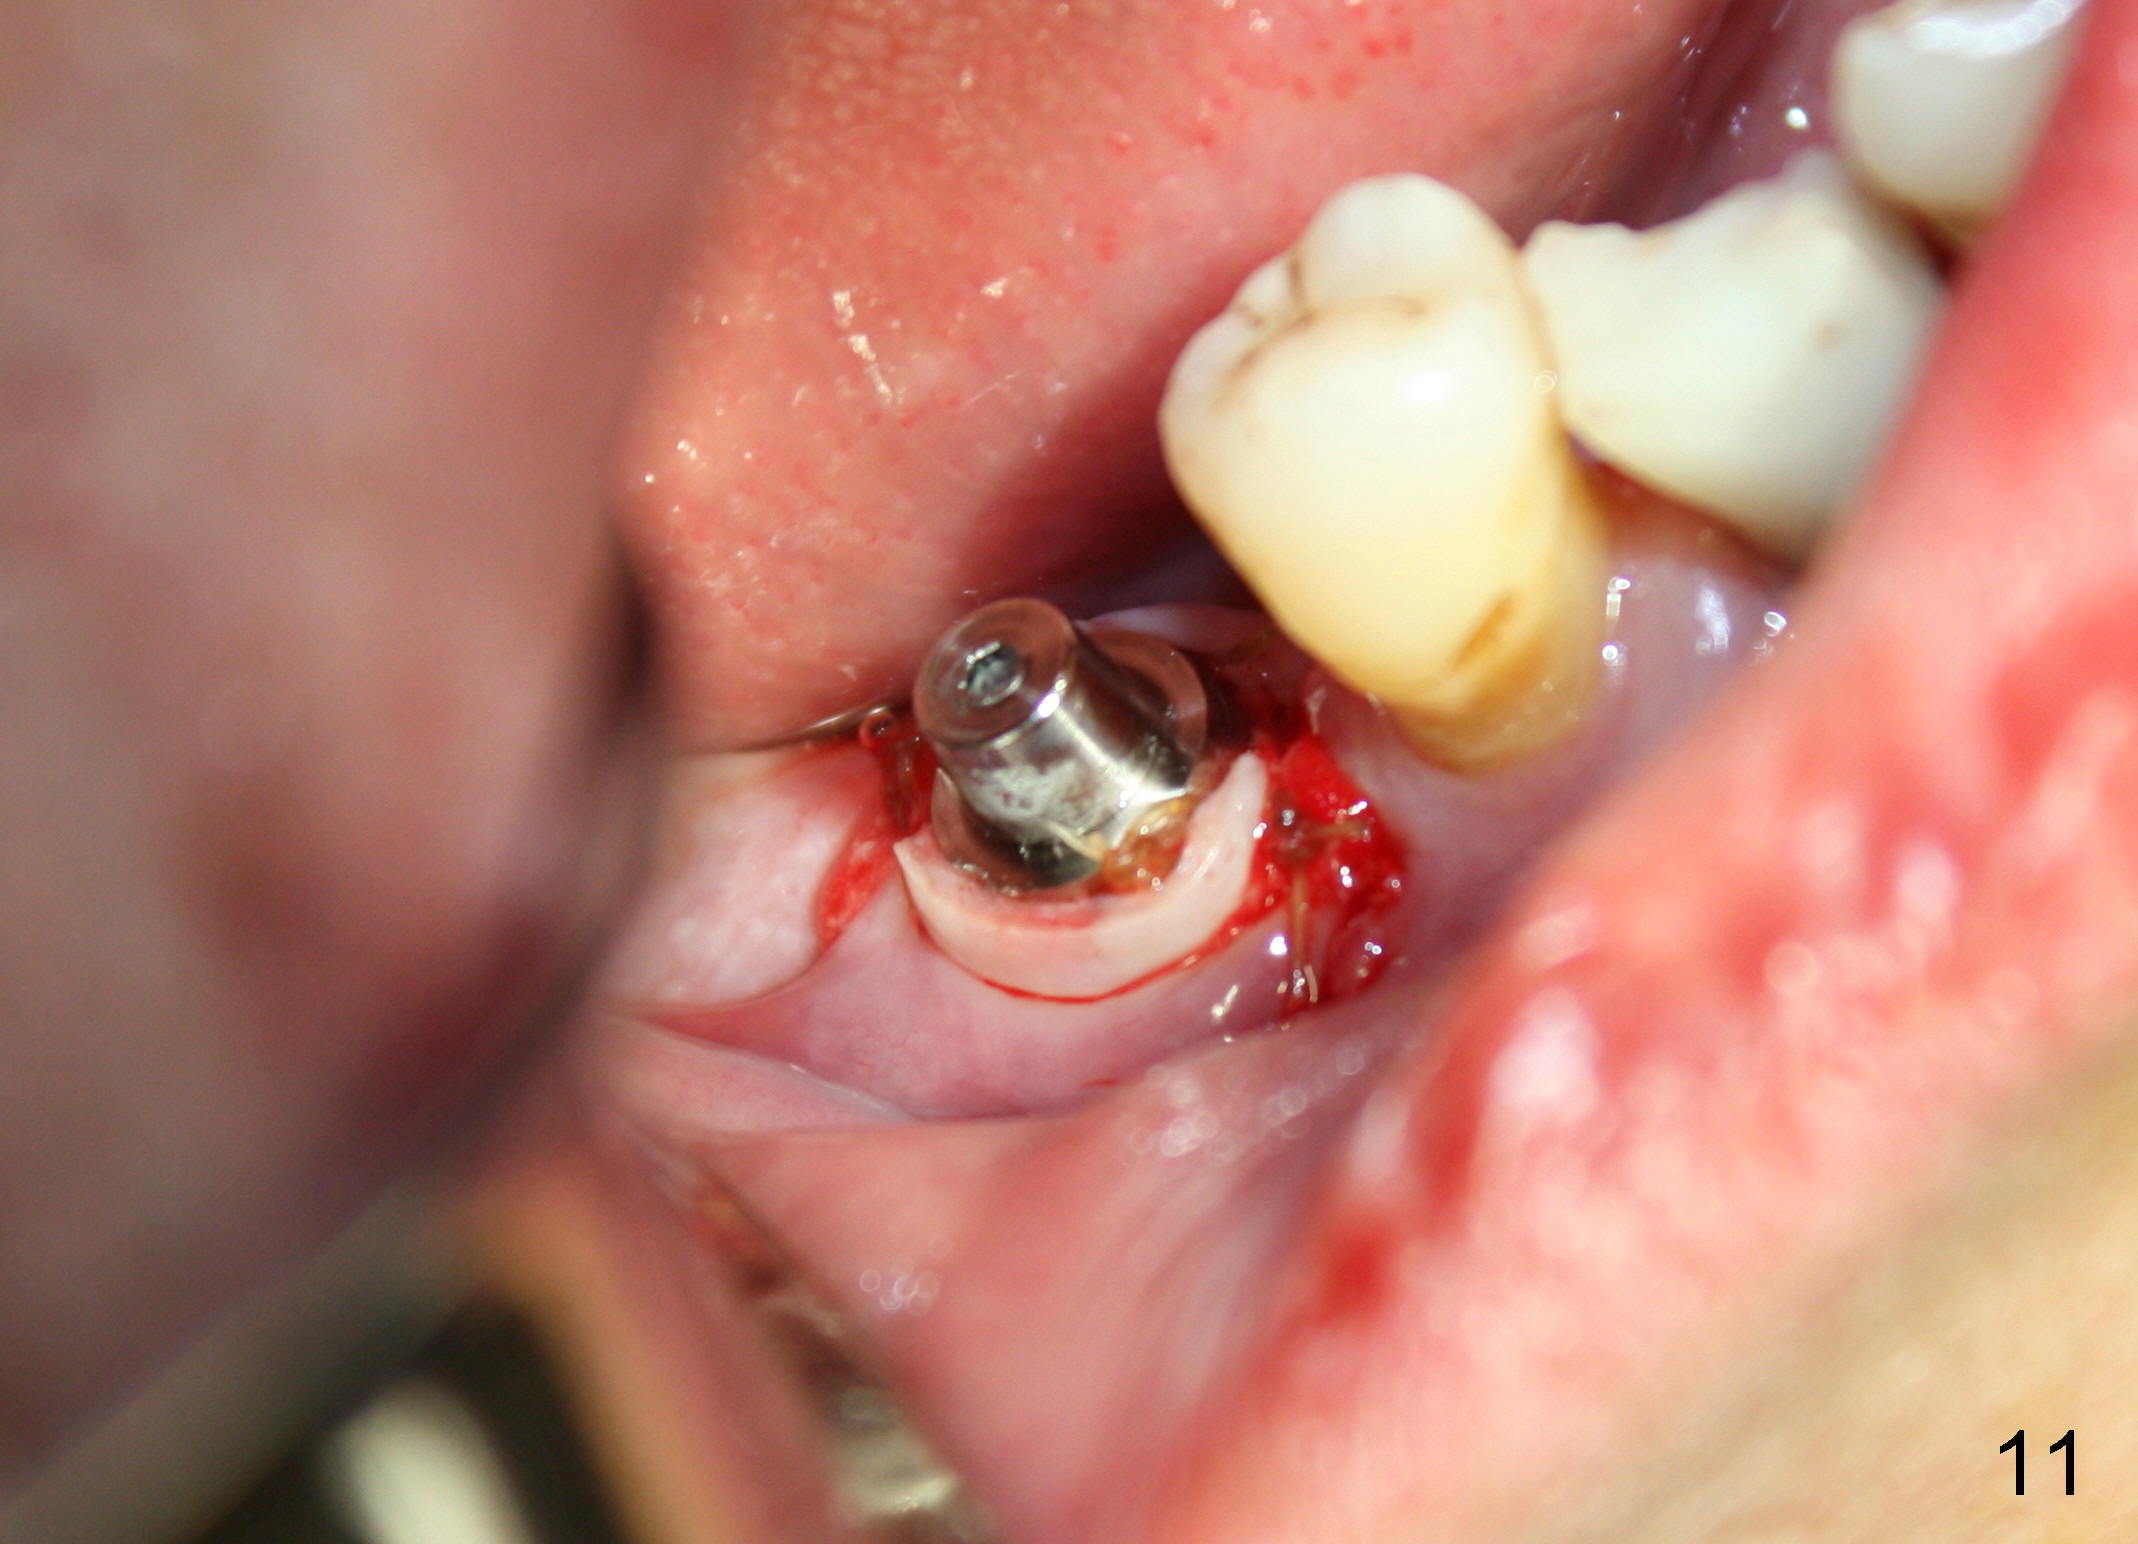

CBCT studies show that a 6x11 mm implant can be safely placed at the site of the tooth #30 (Fig.1 (coronal), 2 (sagittal section). Osteotomy is initiated by 2 mm pilot drill at the depth of 8 mm from the crest (the prospective implant is 3 mm above the crest); X-ray is taken with a parallel pin (Fig.3 P). It appears that there is 12 mm of bone from the crest to the upper border of the inferior alveolar nerve canal. The depth of osteotomy is accordingly adjusted to 11 mm below the crest; osteotomy finishes with insertion of 6x14 mm tap (Fig.4); the patient feels pressure while the tap is being inserted. Following further infiltration with Lidocaine, the depth of the osteotomy is intended to increase in order to bury the implant deeper, because the coronal portion of the buccal plate starts to perforate. The patient feels pain. Finally a 6x14 mm implant is placed ~ 1 mm above the inferior alveolar canal (Fig.5). As mentioned earlier, the rough surface of the implant is exposed buccally (Fig.6 between arrowheads). The nearby buccal plate is decorticated (Fig.7). The autogenous bone harvested during osteotomy (Fig.8) is going to be placed over the exposed portion of the rough surface of the implant (Fig.9); the graft is covered by collagen dressing (Fig.10). The buccal and lingual flaps are approximated with sutures mesial and distal to the implant (Fig.11). To increase the retention of perio dressing, a 4x3 mm abutment is placed.